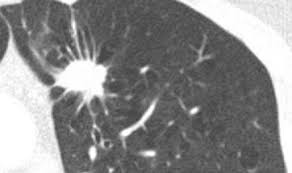

Solitary Pulmonary Nodules

A solitary pulmonary nodule is a radiological finding of a well demarcated opacity less than 3 cm in size on chest x-ray (CXR) or computed tomography (CT) that presents without associated pleural effusion, adenopathy, or atelectasis.

CXR is strongly suggestive of a benign processes if the nodule demonstrates:

Size < 2 cm

Diffuse, popcorn, or concentric calcifications

Clearly demarcated edges

A solitary pulmonary nodule has a higher probability of malignancy if it demonstrates:

Size > 2 cm

Asymmetric calcification

Spiculation or corona radiata: